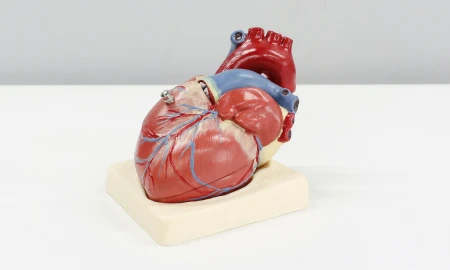

Maladies parodontales et maladies cardiovasculaires

Les maladies parodontales peuvent interférer avec la santé en général, et inversement la santé en général peut favoriser le développement des maladies parodontales. Le facteur principal des maladies cardio-vasculaires est l’artériosclérose, c’est-à-dire un rétrécissement des artères consécutif à l’accumulation de cholestérol et de calcium.

Cardiopathie

Les maladies cardio-vasculaires représentent 40 % des décès et sont la première cause de mortalité dans les pays industrialisés.

Le facteur principal des maladies cardio-vasculaires est l’artériosclérose, c’est-à-dire un rétrécissement des artères consécutive à l’accumulation de cholestérol et de calcium.

Les infections parodontales peuvent avoir une incidence sur les maladies cardio-vasculaires.

Des études récentes menées chez des patients atteints de maladie parodontale suggèrent un risque accru de pathologie cardiaque avec en particulier un doublement du risque d’infarctus par rapport aux patients indemnes de maladie parodontale.

Des recherches complémentaires sont en cours pour préciser le mécanisme d’action des bactéries parodontales. Une première hypothèse est que les bactéries passent dans le sang circulant, à partir de gencives inflammées et forment de petits caillots sanguins qui contribuent à obstruer les artères. L’autre hypothèse est liée à l’inflammation provoquée par les bactéries parodontales qui contribuerait à la formation de dépôts graisseux dans les artères coronaires.

La prévention ou le traitement initié dès qu’une maladie parodontale est diagnostiquée sont requis, en particulier chez les patients présentant un risque cardiaque.